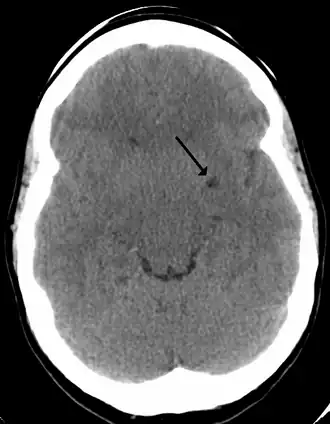

![]() A perivascular space as seen on CT | |

A perivascular space, also known as a Virchow–Robin space, is a fluid-filled space surrounding certain blood vessels in several organs, including the brain,[1] potentially having an immunological function, but more broadly a dispersive role for neural and blood-derived messengers.[2] The brain pia mater is reflected from the surface of the brain onto the surface of blood vessels in the subarachnoid space. In the brain, perivascular cuffs are regions of leukocyte aggregation in the perivascular spaces, usually found in patients with viral encephalitis.

In humans, perivascular spaces surround arteries and veins can usually be seen as areas of dilatation on MRI images. While many normal brains will show a few dilated spaces, an increase in these spaces may correlate with the incidence of several neurodegenerative diseases, making the spaces a topic of research.[4]

Perivascular spaces are distinguished on an MRI by several key features. The spaces appear as distinct round or oval entities with a signal intensity visually equivalent to that of cerebrospinal fluid in the subarachnoid space.[7][14][15] In addition, a perivascular space has no mass effect and is located along the blood vessel around which it forms.[14]